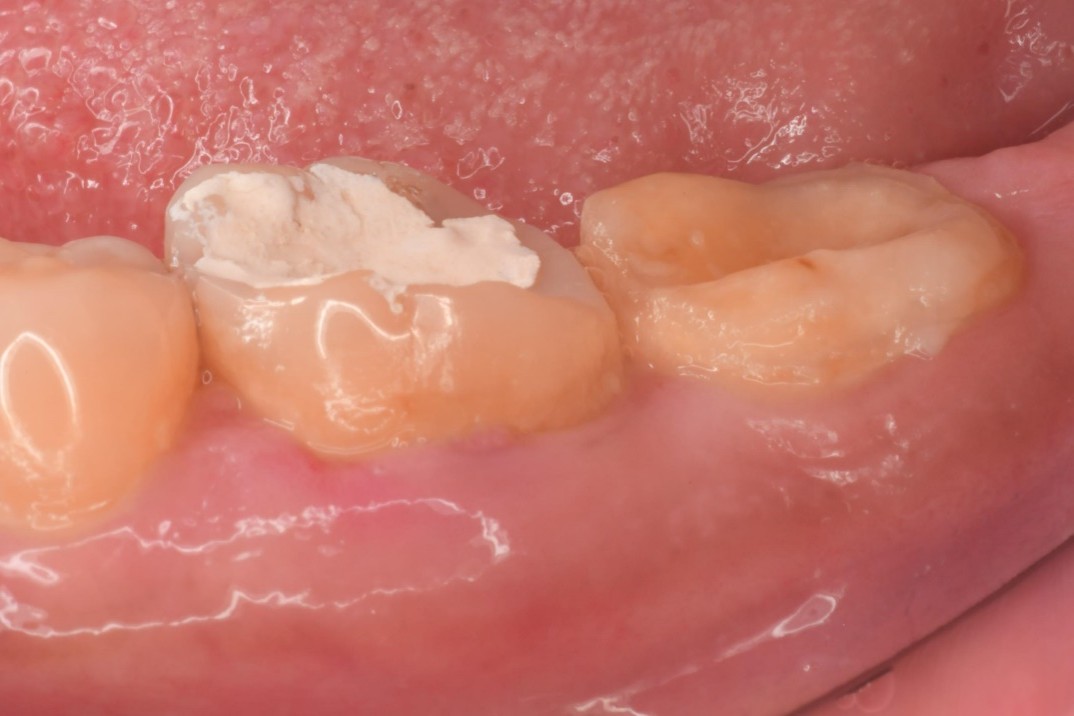

陶瓷崁體-二次蛀牙-#3646

審美牙科

瓷塊-崁體